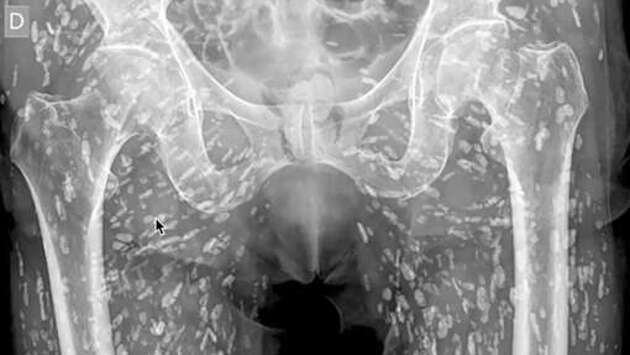

OC: рентген показал сотни кальцинированных яиц ленточного червя в теле пациента

Доктор поделился рентгеновским снимком человека, зараженного кальцинированными яйцами ленточного червя, пишет Oddity Central. Недавно врач отделения неотложной помощи Сэм Гали опубликовал уникальный рентгеновский снимок, который он назвал "одним из самых невероятных" за всю свою карьеру. На снимке видно, что нижняя часть тела пациента буквально усеяна сотнями кальцифицированных яиц ленточного червя. Ленточные черви — это паразиты, которые обычно обитают в кишечнике, питаясь питательными веществами. Однако мало кто знает, что их яйца могут мигрировать по всему организму, включая мышцы, жировую ткань и даже мозг, а их присутствие в тканях может вызывать серьезные осложнения. Как объяснил Гали, специализирующийся на сердечно-сосудистых неотложных состояниях и радиологии, случай пациента связан с заболеванием, известным как цистицеркоз. При этом пациент даже не подозревал о своем состоянии. Он обратился за медицинской помощью после падения и жалоб на боль в бедре. Чтобы избежать подобного заражения, врачи рекомендуют воздерживаться от употребления сырой или недостаточно приготовленной свинины и рыбы, а также соблюдать правила гигиены.